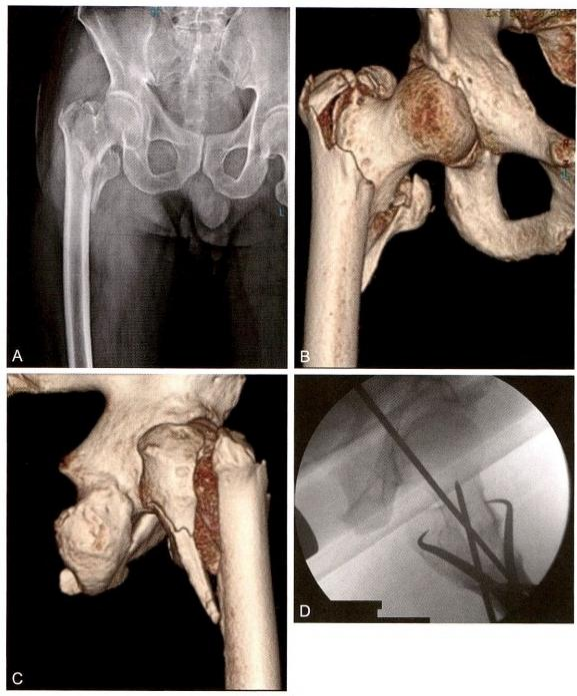

图9-10 点状复位钳夹固定。 A.术前X 线 ;B. 术前CT 正位;C. 术前CT 侧位;D. 钳夹复位后侧位透视

图9-11 难复型病例。A 、B.术前CT;C. 牵引后正位示复位不良,近端矢状位旋前;

D. 牵引后侧位复位不良,近端向前移位;E 、F. 采用多种复位方法后

4)术中复位技巧4:对于难复型病例,可以综合运用多种方法复位, 此类简单骨折(AO 分型A1.2, 即2007版的A1.3) 复位非常困难。往往 由于复位不良,导致手术失败(图9-11A 、B); 牵引后正位复位不良, 近端矢状位旋前(图9-11C); 牵引后侧位复位不良,近端向前移位(图 9-11D) 。用点状复位钳钳夹复位,正、侧位良好,并用克氏针临时固定, 然后常规髓内钉导针定位(图9-11E、F)。复位之后,需采用复位质量标准进行评价(表9-3、表9-4)。在开口 之前,不可接受的复位需要继续调整。